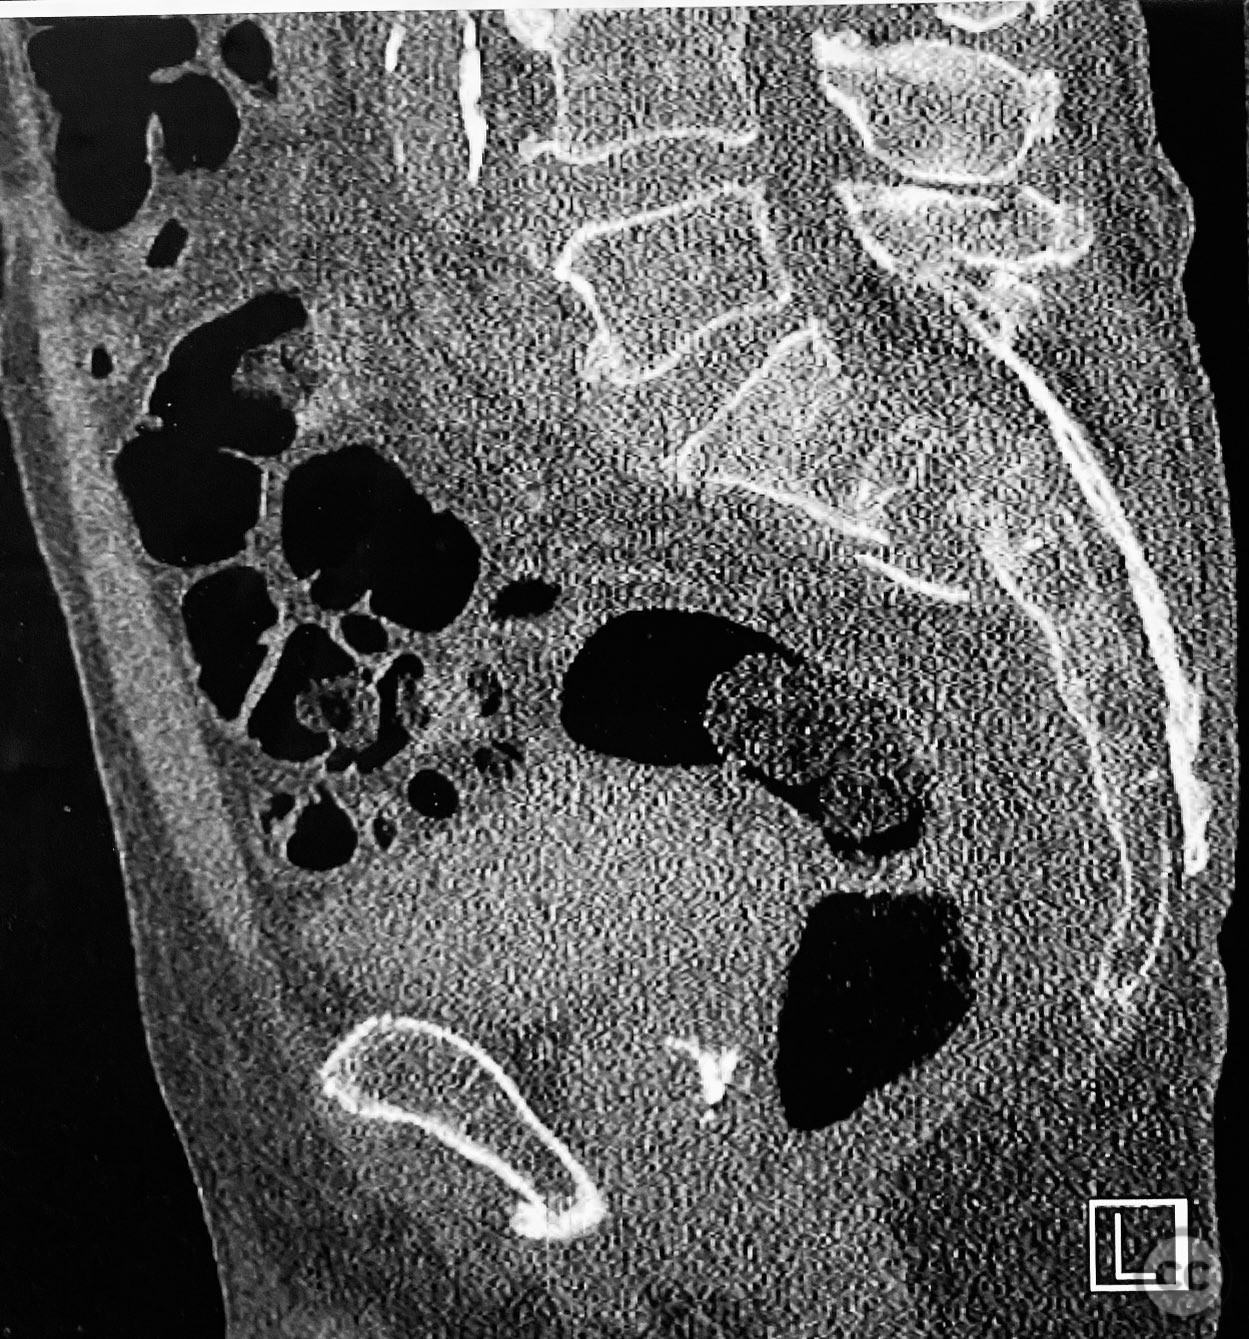

Clinical and radiological findings:  An elderly patient presented with a complex upper sacral fracture characterized by oblique fracture pathways bilaterally, described as a "UYH+pattern" fracture. The patient exhibited compromised bone quality consistent with age-related osteopenia or osteoporosis. Initial clinical assessment prioritized pain control and early mobilization. Radiological evaluation, including computed tomography (CT), confirmed the oblique orientation of the upper sacral fracture lines and their bilateral extension. No neurovascular compromise was reported.

Anatomical surgical approach:  Percutaneous access was established over the dorsal aspect of the pelvis. Small incisions were made lateral to the sacrum, and soft tissue dissection was performed to the level of the os sacrum. Guide pins were advanced under fluoroscopic control along the oblique upper sacral corridors bilaterally. The cannulated CurvaFix device was inserted over each guide pin, articulated to match the oblique fracture pathway, and subsequently locked in situ according to the manufacturer’s specifications.

The articulated nature of the CurvaFix device allowed precise accommodation of the complex oblique upper sacral fracture pathways bilaterally. Percutaneous technique minimized soft tissue disruption and surgical morbidity. Postoperative CT imaging confirmed satisfactory device placement and fracture reduction. The achieved stability provided immediate pain relief, reduced or eliminated narcotic requirements, and enabled early mobilization. Surgeons with experience in device removal have reported no technical difficulties.